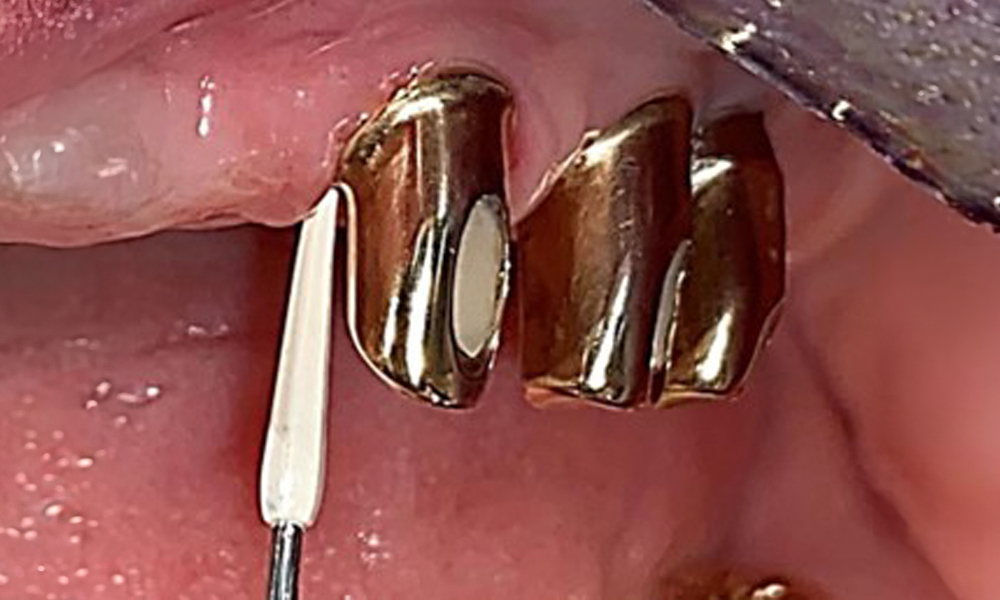

Based on the medical history, the risk of complications is classified as mild to moderate due to the intake of ASA 100 and bisoprolol. It should be noted that increased bleeding may occur during treatment, particularly if gingivitis is present. The risk is classified as low in the present case, as the patient maintains excellent intraoral hygiene. Due to the otherwise stable intraoral status over many years, the needs determined during the intraoral examination will be decisive for her treatment. The findings observed during any dental appointment will determine the subsequent course of treatment. Determination of bleeding status is mandatory to detect gingival changes in peri-implant tissues (Fig. 6).

Probing implant 23 at a probing depth of 4 mm using a plastic probe, showing negative BOP findings and a hyperplastic papilla.

Fig. 6: Probing implant 23 at a probing depth of 4 mm using a plastic probe, showing negative BOP findings and a hyperplastic papilla.

The periodontal status should be thoroughly examined once a year. This examination provides comprehensive documentation of the periodontal and implant findings, including pocket depths, periodontal recession and furcation involvement. This will ensure a rapid response to any potential progression of the mucositis, gingivitis, periodontitis or peri-implantitis. Implant probing using a plastic probe is recommended. In the present case, a mesial probing depth of 4 mm was detected mesial to implant 23. No suppuration or bleeding was detected, indicating the absence of peri-implantitis.